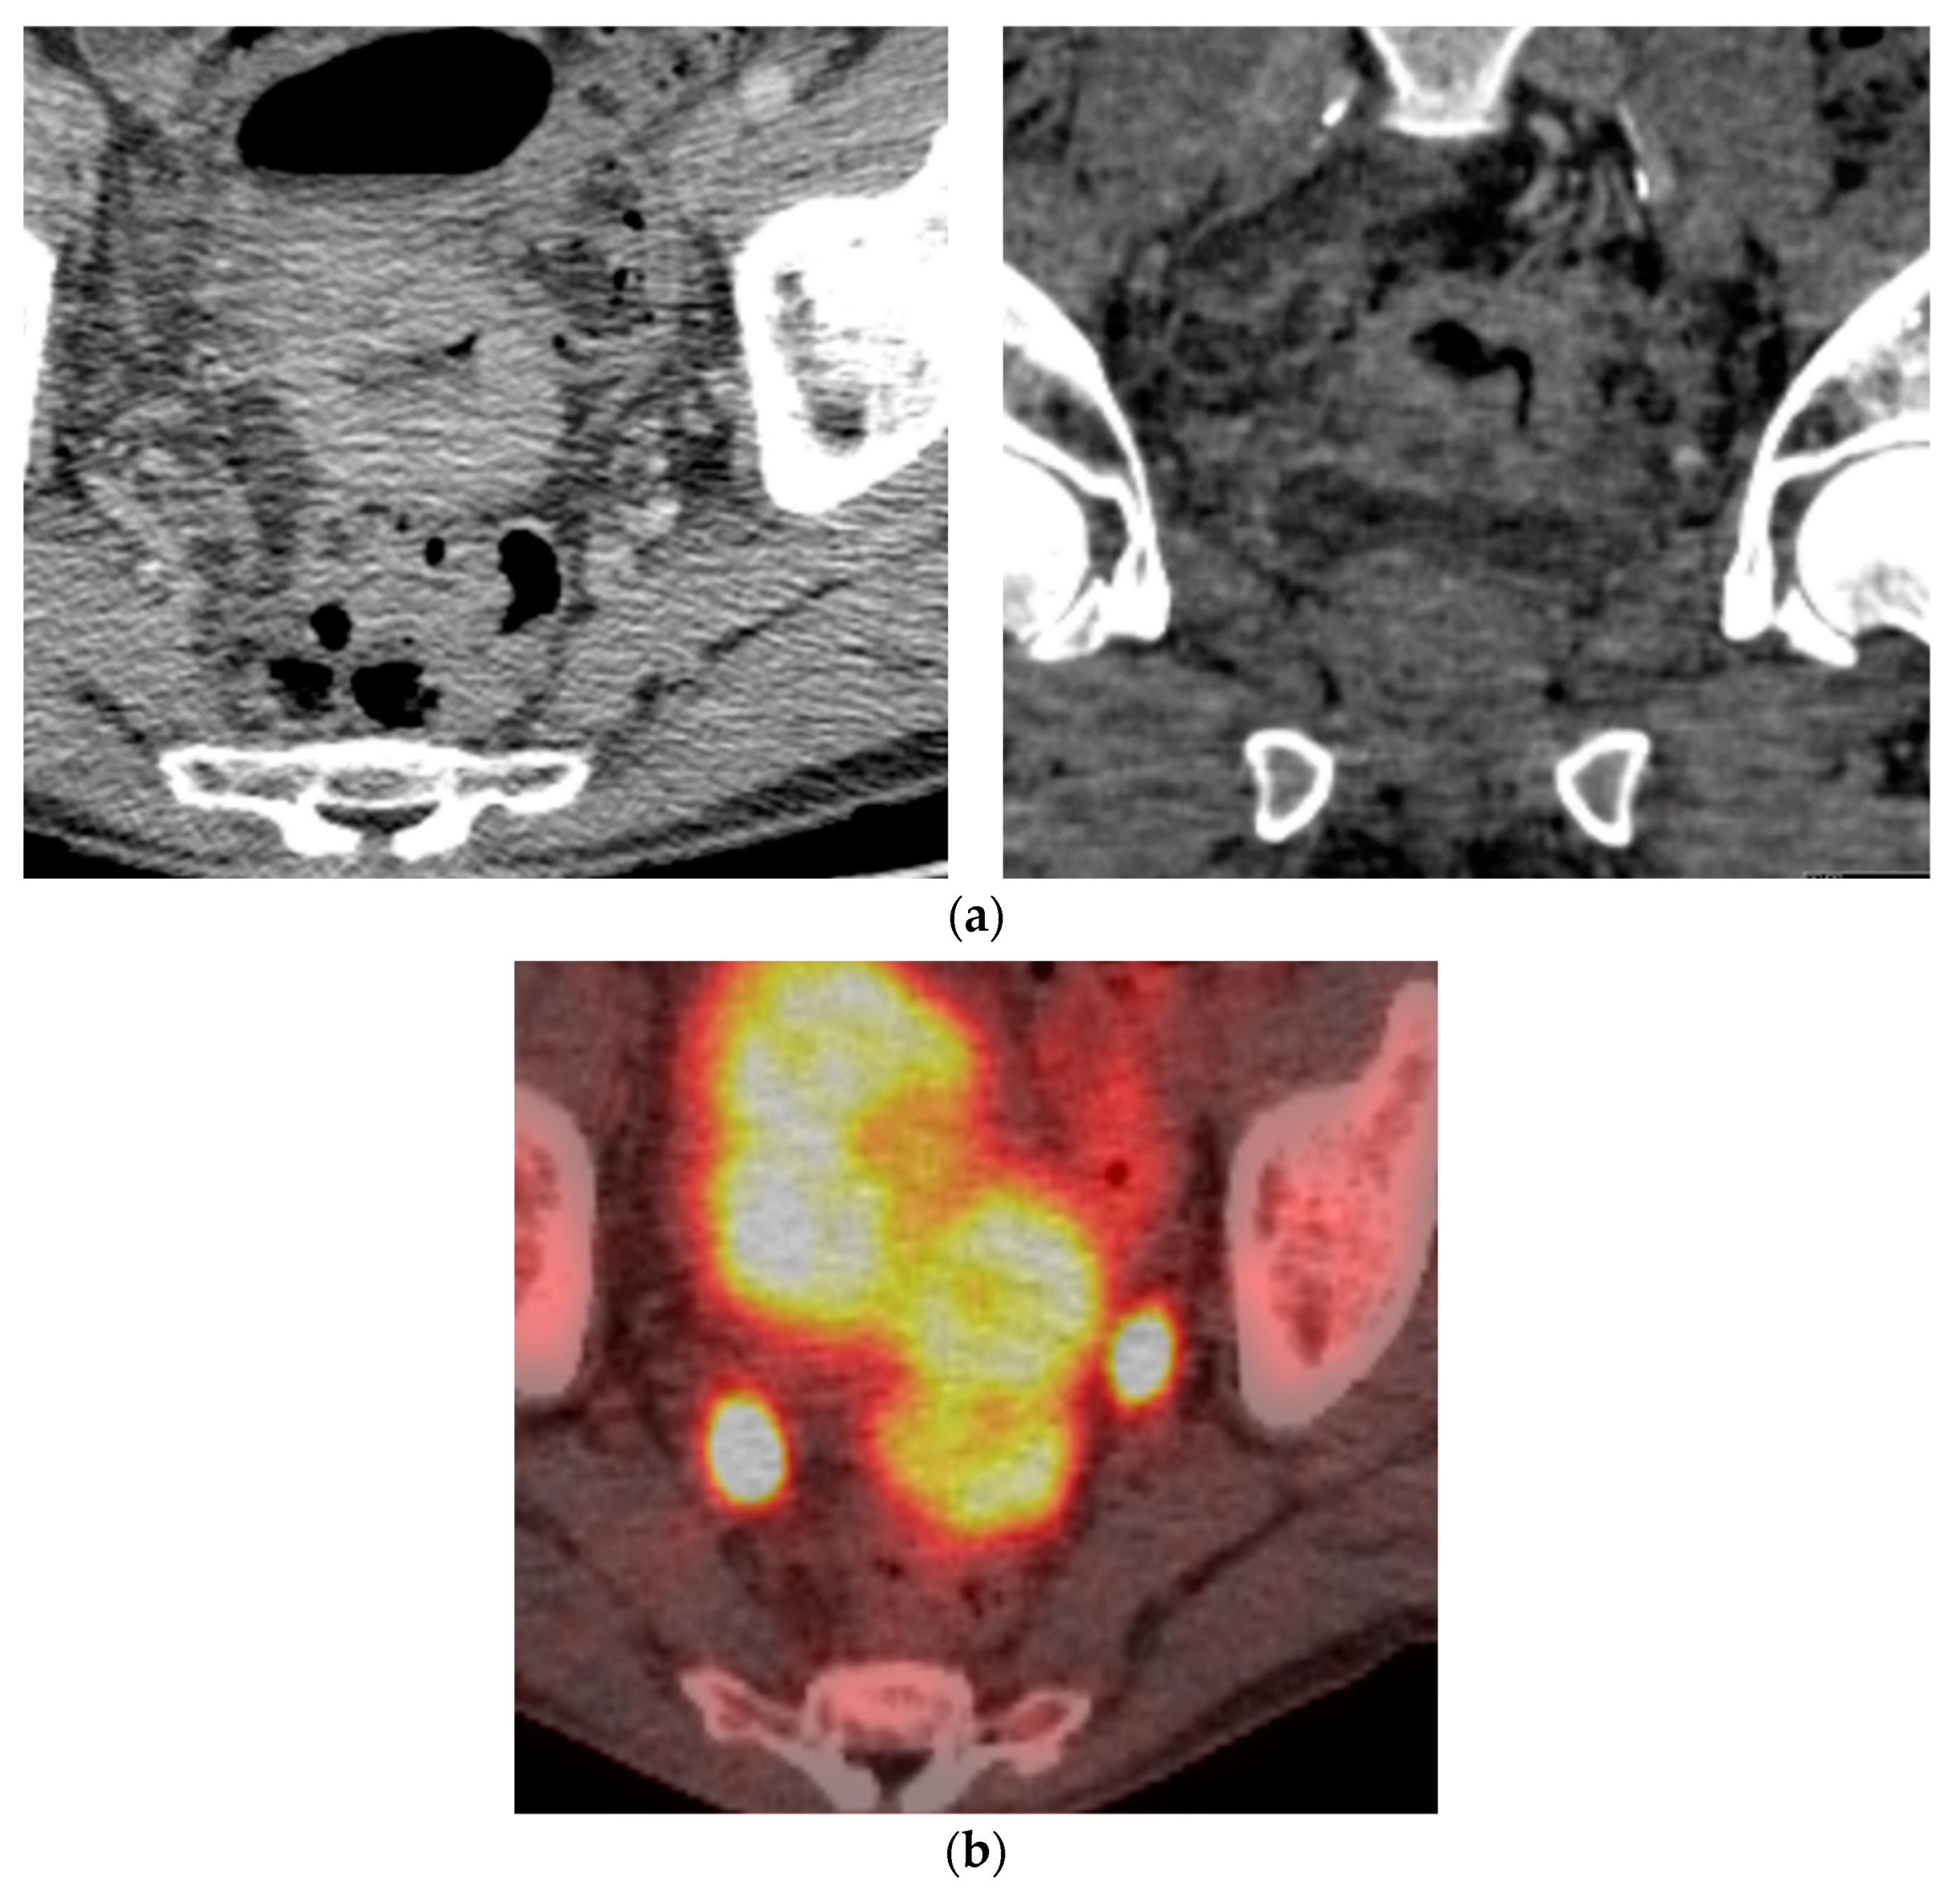

11. Testis

- Berrondo, C.; Gorman, T.E.; Yap, R.L. Primary plasmacytoma of the testicle: A case report. J. Med. Case Rep. 2011, 5, 494. [Google Scholar] [CrossRef] [PubMed]

- Bude, R.O. Testicular plasmacytoma: Appearance on gray-scale and power Doppler sonography. J. Clin. Ultrasound 1999, 27, 345–346. [Google Scholar] [CrossRef]

- Hathaway, A.R. Incidental discovery of a testicular plasmacytoma at initial presentation of multiple myeloma. Case Rep. Hematol. 2013, 2013, 752921. [Google Scholar] [CrossRef]

- Bortolotto, C.; Ori-Belometti, G.; Rodolico, G.; Draghi, F. Plasmacytoma of the testis in a patient with previous multiple myeloma: Sonographic appearance. J. Ultrasound 2016, 19, 153–155. [Google Scholar] [CrossRef] [PubMed]

- Lue, K.; Emtage, J.B.; Parinas, M.A.; Dhillon, J.; Pow-Sang, J. An extramedullary plasmacytoma in the testicle: A case report and review of the literature. Can. Urol. Assoc. J. 2015, 9, E240–E242. [Google Scholar] [CrossRef] [PubMed]